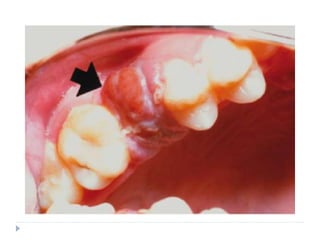

CLINICAL PRESENTATION

 Facial swelling and proptosis

 Pain, tenderness and paraesthesia are minimal

 Tooth mobility is common : because of aggressive

destruction of the alveolar bone

 Premature exfoliation of the deciduous teeth

 Enlargement of the gingiva and alveolar processes

are other common symptoms